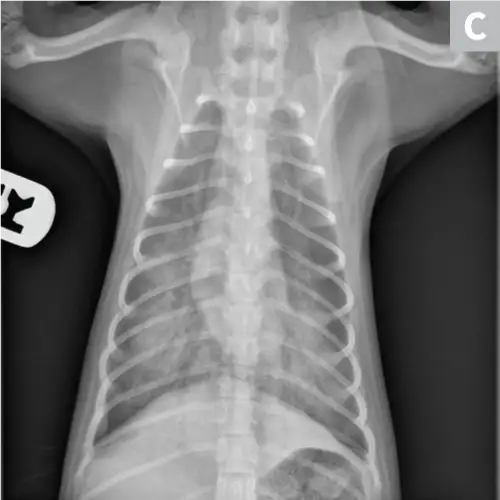

Radiographs may reveal a diffuse, unstructured interstitial pattern (Figure 9). Subtle changes in interstitial opacity may go unnoticed despite severe histologic disease.62

Featured Image

FIGURE 9

Idiopathic pulmonary fibrosis with a diffuse bronchointerstitial pattern. Idiopathic pulmonary fibrosis was confirmed on lung biopsy.